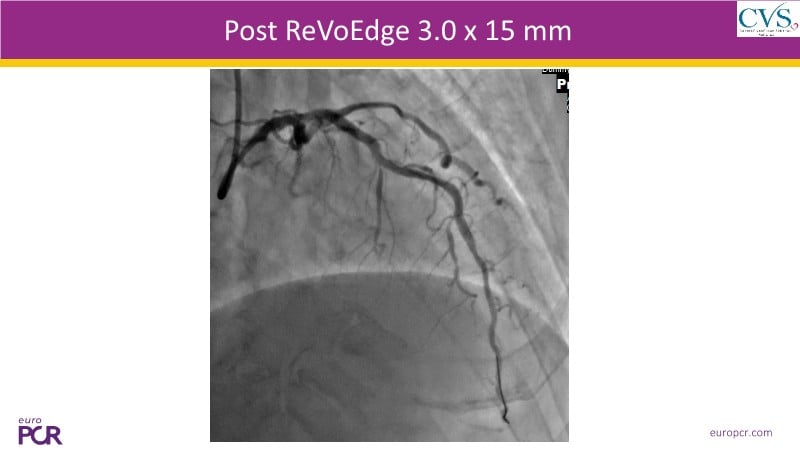

Discover how the next-generation RevoEdge high-pressure cutting balloon is transforming PCI with innovative design and proven clinical outcomes. This session presents a multicenter randomised trial and real-world case discussions, showcasing RevoEdge’s effectiveness in tackling resistant, complex lesions—including long, tortuous, and fibrotic cases. Learn practical tips, tricks, and intravascular imaging insights to optimize lesion preparation and improve patient outcomes. Don’t miss this opportunity to see how RevoEdge helps you cut through challenges and conquer PCI complexities.

- To learn about the clinical benefits and tips and tricks of using RevoEdge high pressure cutting balloon in different types of complex lesions through case-based discussion